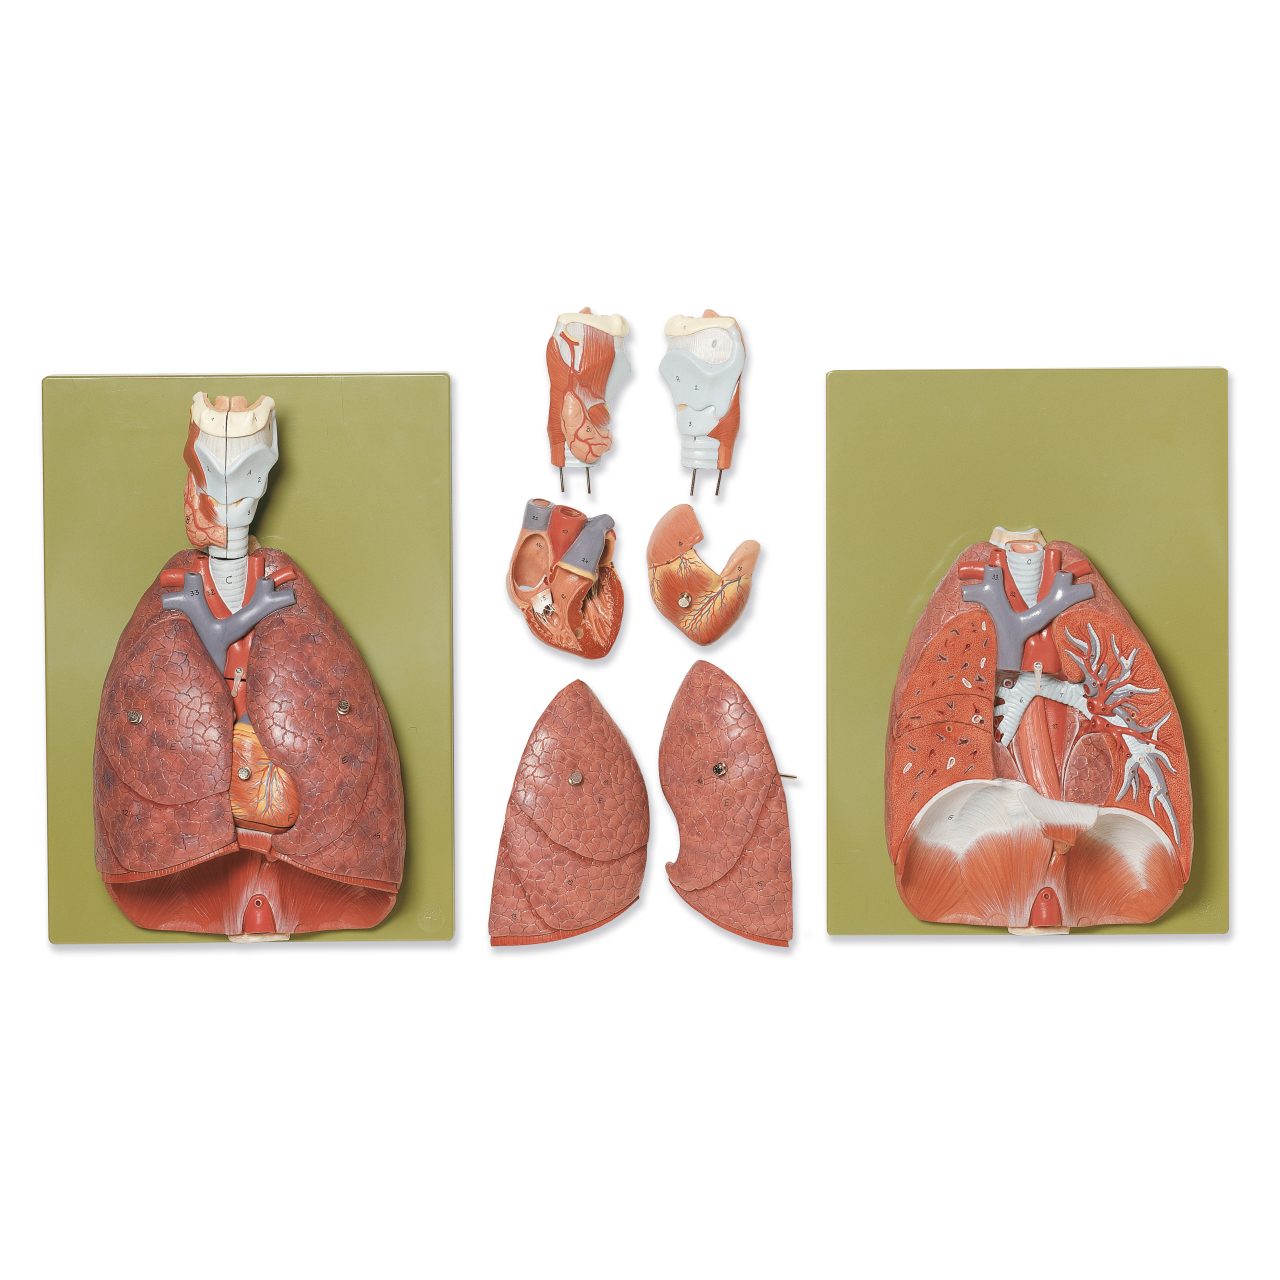

Lungs With Heart, Diaphragm and Larynx

- ¾ natural size, in SOMSO-PLAST®

- The model shows the viscera of the thorax

- Separates into 7 parts:

- Right and left lungs

- Heart (2 parts)

- Larynx (2 parts)

- Base model

- Bifurcation of the trachea and oesophageal hiatus with aortic hiatus in the diaphragm is demonstrated

- On a green base

- H 39 cm, W 28 cm, D 72 cm

- Weight 2.4 kg